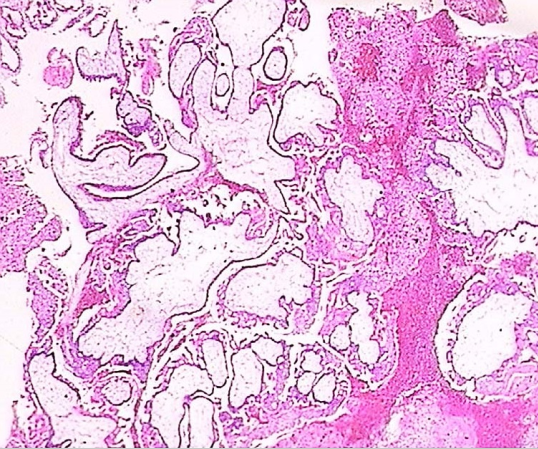

完全性葡萄胎大体观 完全性葡萄胎镜下观(100×)

见绒毛增大伴中央空没事形成及滋养细胞增生